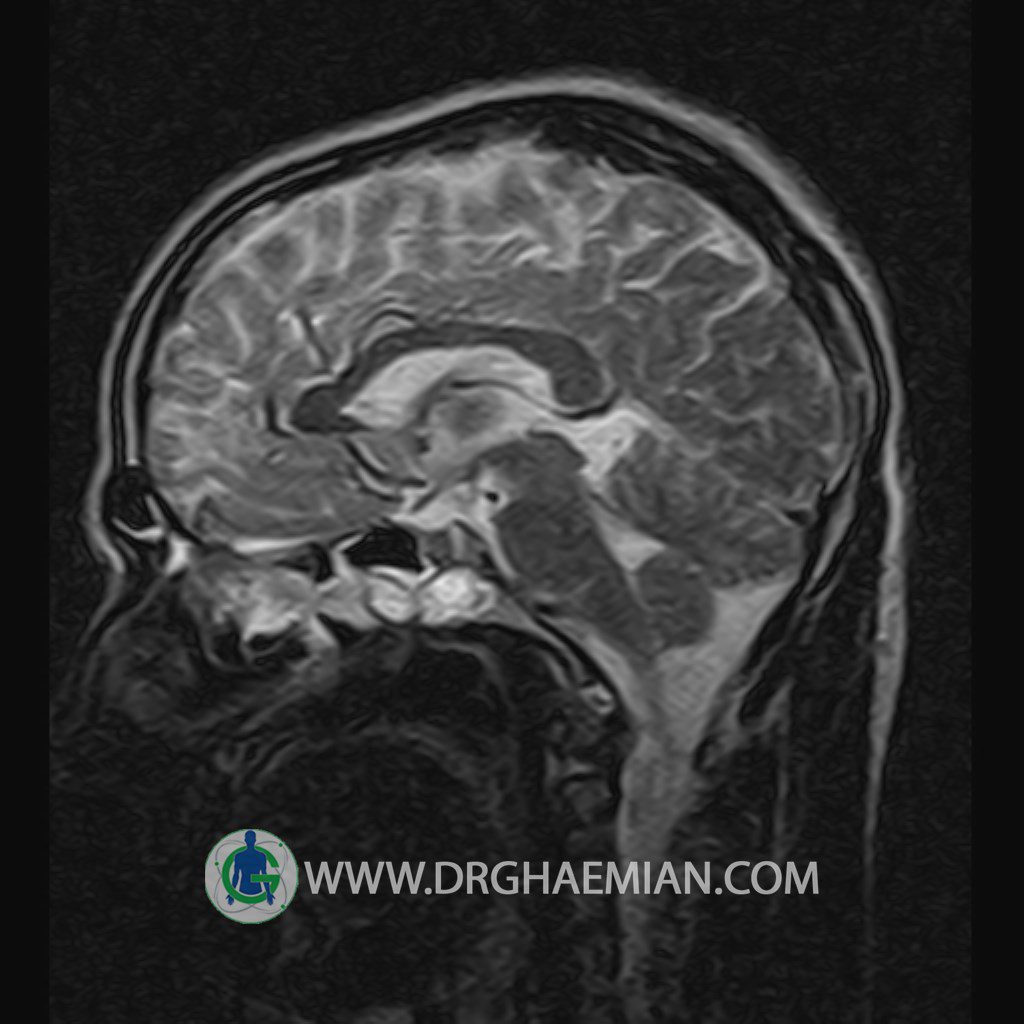

پزشکان اغلب از تصویربرداری ام آر آی برای تشخیص و درمان عارضه های پزشکی که فقط با استفاده از اشعه ایکس یا میدان مغناطیسی و امواج رادیویی قابل مشاهده است، استفاده می کنند. دستگاه ام آر آی تصاویر دقیق از ساختار های داخلی بدن ایجاد می کند. در این کیس یک میکروآدنوم در هیپوفیز بیمار مشاهده می شود.

HYPOPHYSIS MRI

(with and without contrast)

Technique: Axial , coronal T1 , Axial , coronal , sagittal T2 , Axial, coronal T1 post Gd & 64 dynamic thin coronal slices.

Imaging of the hypothalamus after contrast medium administration was normal.

– Small hypoenhancing mass lesion ( 3 x 4 mm ) in posterior of pituitary stalk suggestive for micro adenoma